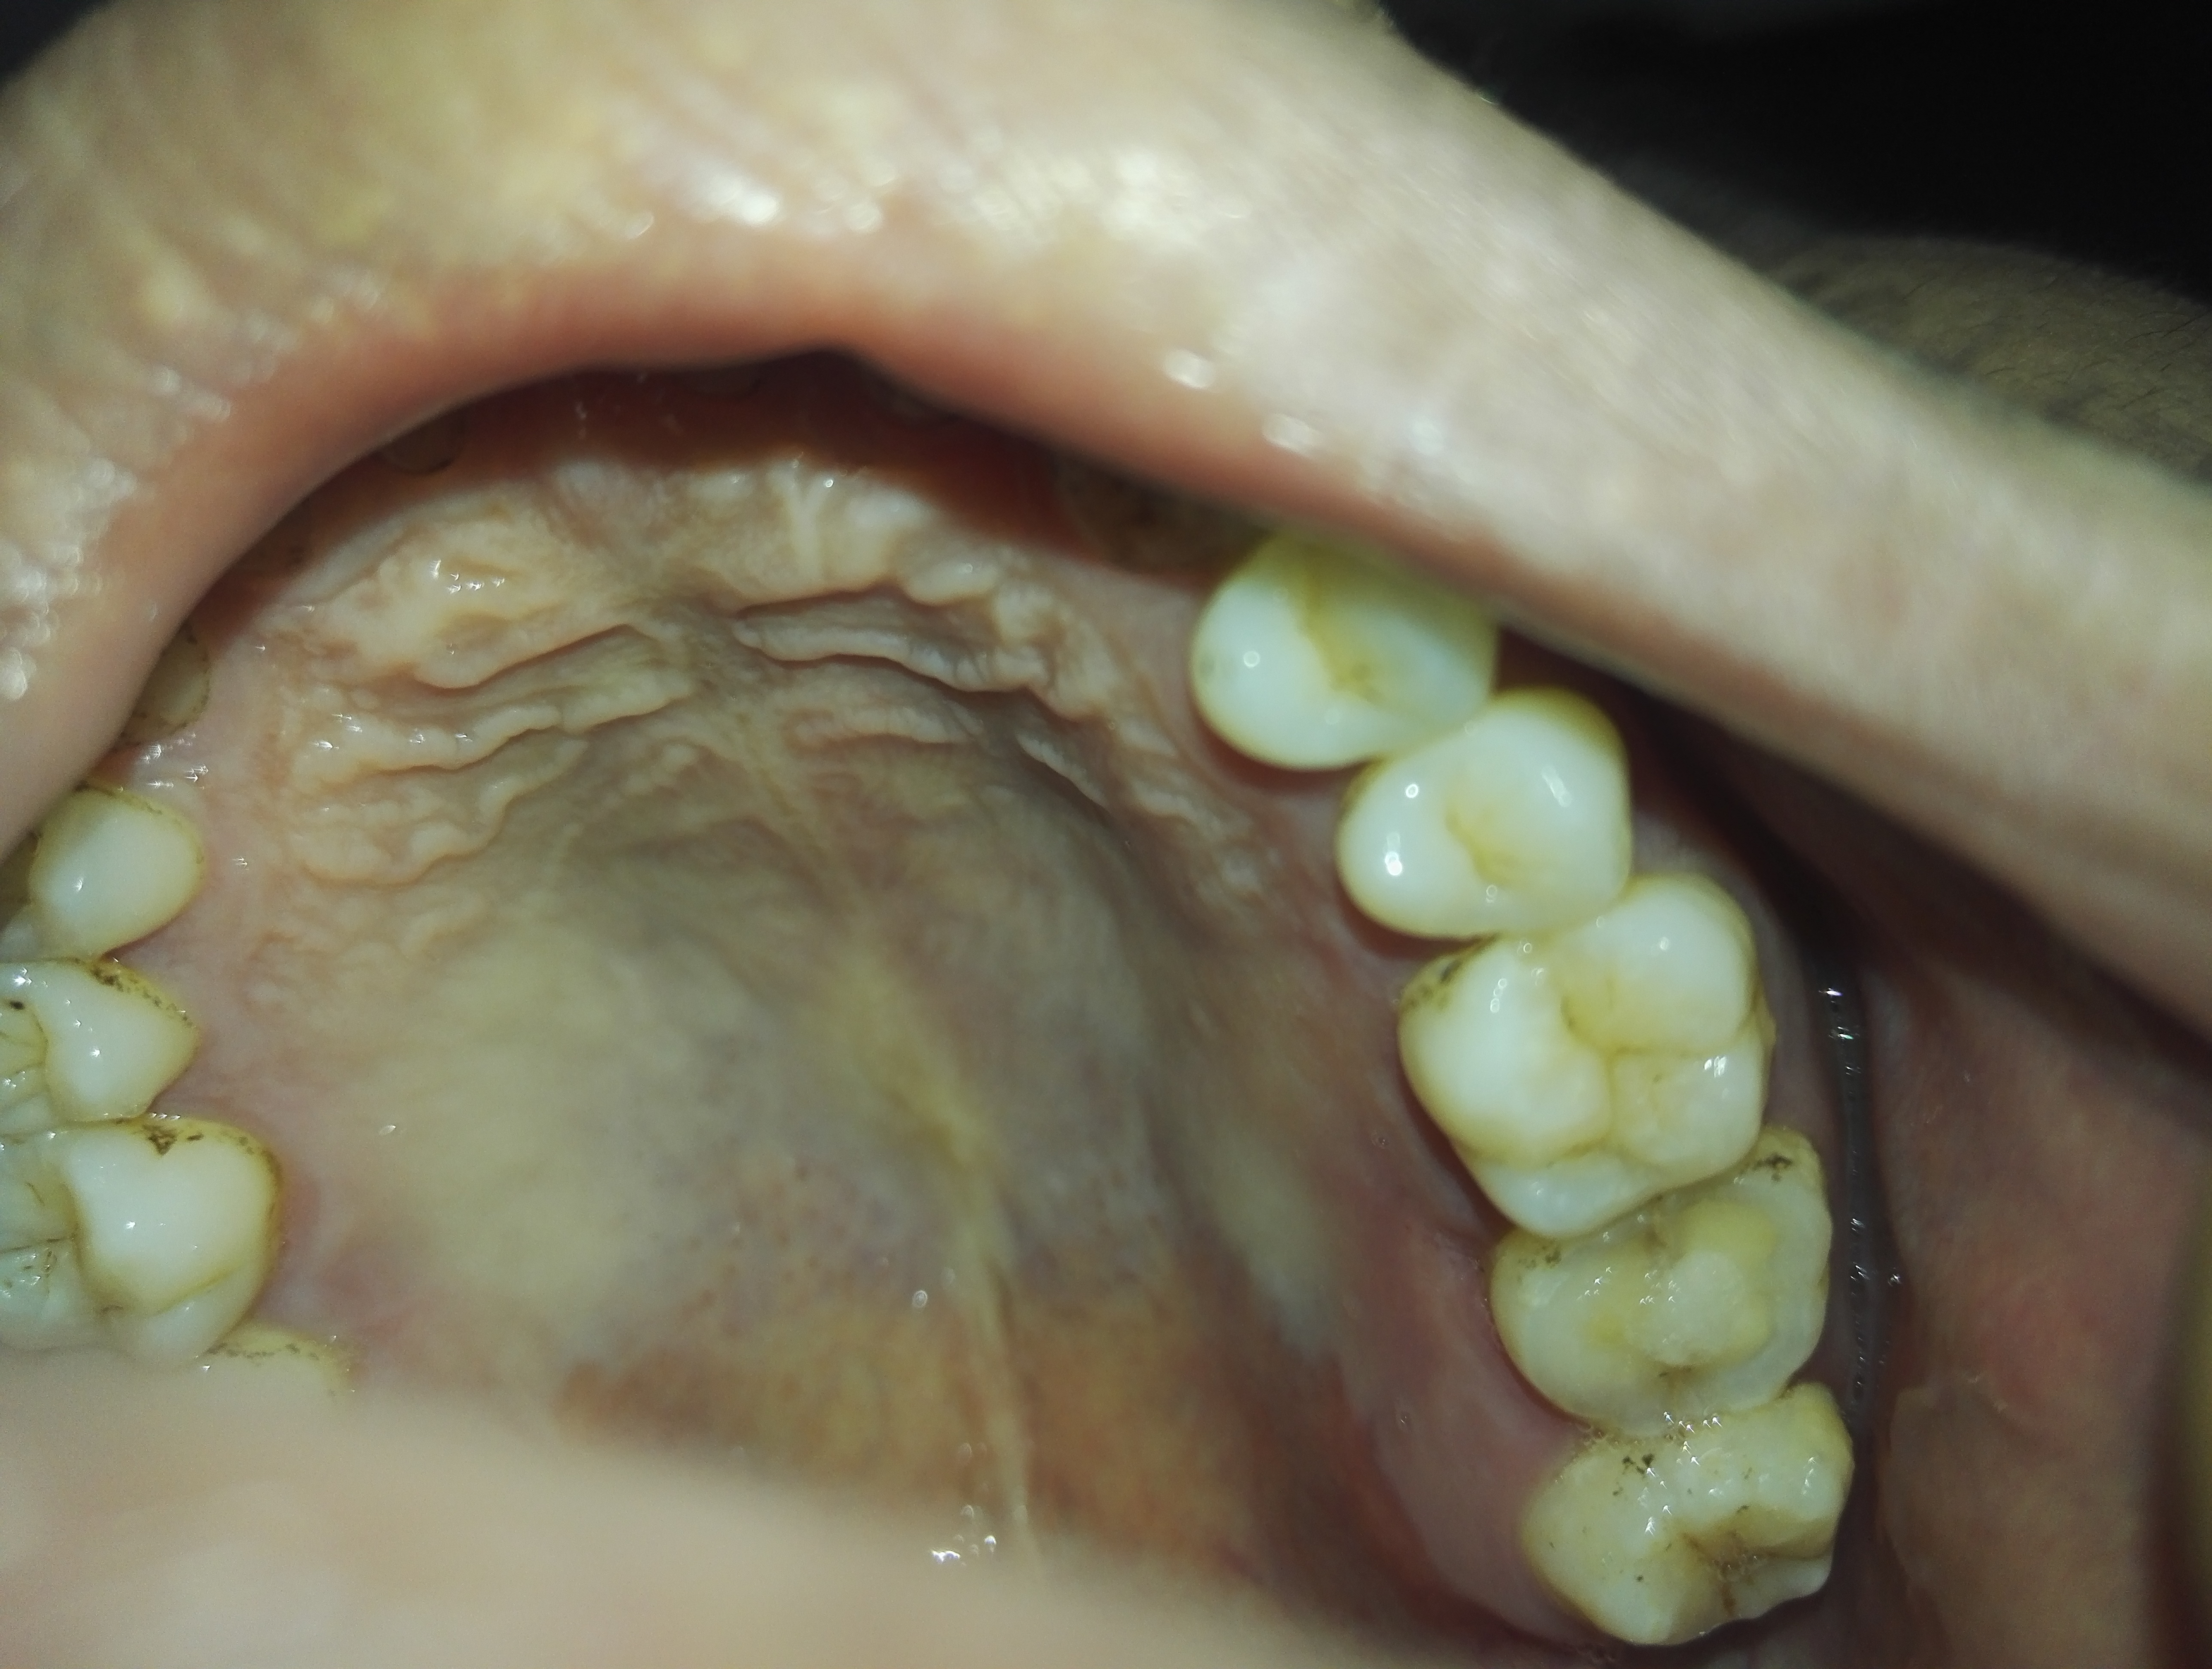

牙痛特别厉害,半个脑壳一直在抽痛,去医院检查医生说牙齿裂了,现在医生给我做的是什么,牙磨掉了差不多一半了,要去复诊四五次,费用大概差不多一千

已经医好了,去5次医院花了一千三,把原来的牙齿磨短了,套了一颗新牙齿。